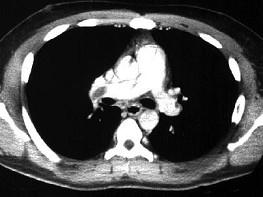

问题 男,28岁,突发呼吸困难,结合影像图像,选择最可能的诊断 ( )

选项 A、右肺中央肺癌并右上肺不张,淋巴转移 B、右上肺小叶性肺炎 C、右上肺奇叶 D、右主肺动脉栓塞 E、右上肺大叶性肺炎

答案 D